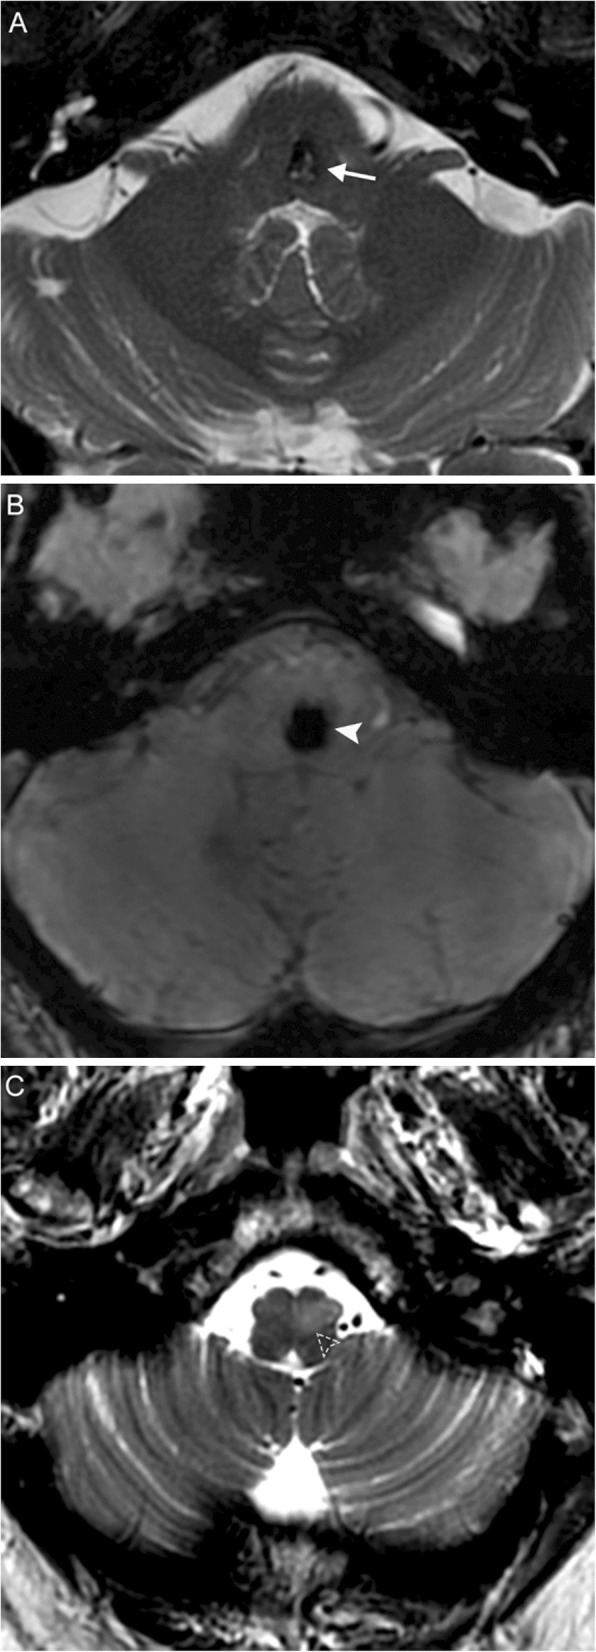

MRI is characterized by distinct phases of progression. The ION initially appears normal, then develops T2-hyperintensity after 1 month. After several months to a few years, the ION remains T2-hyperintense and also becomes hypertrophic; this hypertrophy eventually resolves, and the ION becomes atrophic. Contrast enhancement is atypical (Fig. 10).

Fig. 10.

Hypertrophic olivary degeneration. A 69-year-old man with history of hypertension presenting with new onset palatal myoclonus, hoarse voice, and ataxia. Axial T2 (a) and susceptibility-weighted (b) MR images reveal a lesion at the left parasagittal pontomedullary junction at the level of the facial colliculus demonstrating bubbly high T2 signal internally surrounded by a rim of low T2 signal intensity (arrow) and associated blooming (solid arrowhead), compatible with a cavernous malformation. Thin section axial T2 image (c) reveals hyperintensity and expansion of the left inferior olivary nucleus (dashed arrowhead), consistent with hypertrophic olivary degeneration. Lesions involving the dento-rubro-olivary tract (such as this cavernous malformation) can lead to hypertrophic olivary degeneration